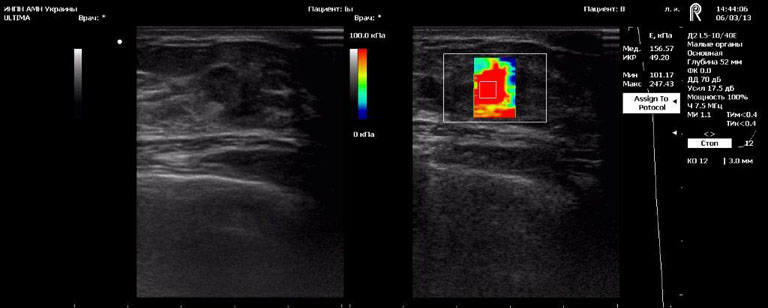

Після комп’ютерної обробки інформація передається на екран монітора, де ділянки з різними механічними властивостями відображаються різним кольором. Таке зображення називається «еластограма». В досліджуваному об’ємі тканин можливо провести кількісні вимірювання і, шляхом порівняння з еталонними значеннями, зробити висновок про наявність патології і її характер. Більш жорсткі тканини відображаються червоним, а м’які — синім кольором. Висока жорсткість утвору при проведенні еластографії свідчить про високу вірогідність його злоякісного походження.

Ехограми

Breast cancer (злоякісна пухлина)